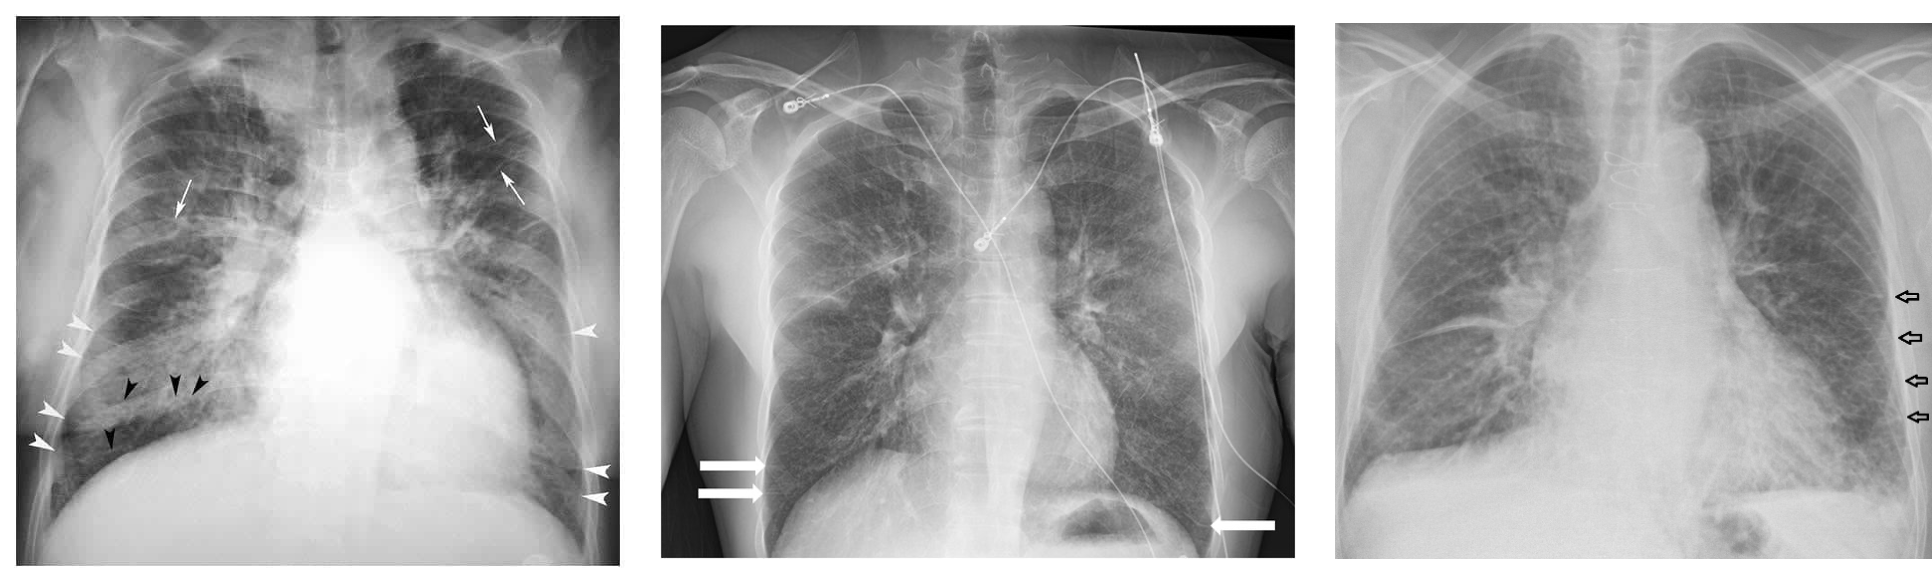

(Image: Cardiomegaly & pulmonary edema)

Cardiomegaly & pulmonary edema

- Chest X ray:

- Cardiomegaly

- Pulmonary edema

- Pleural effusion

Kerly B lines( interstitial edema)

Prominent blood vessels in upper lung field (called cephali sation)

How to calculate Cardiomegaly Horizontal diameter of the heart divided by widest horizontal distance in the chest cavity. If more than 0.5 ⇒ cardiomegaly (How to remember: heart/chest)